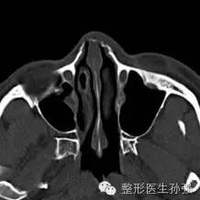

歪鼻怎么造成先天发育、外伤(击打、车祸)歪鼻造成哪些影响外貌、鼻通气障碍歪鼻畸形多大可以治疗鼻部发育完全,通常16-18岁以后歪鼻畸形治疗时机外伤后早期(3周内)行闭合复位,矫正移位的鼻骨、鼻中隔软骨外伤后晚期,先天发育的,行鼻骨截骨矫正、鼻中隔畸形矫正,改善外观、功能。手术可以同时矫正鼻尖、鼻翼吗可以,切取的畸形鼻中隔软骨正好可以用于鼻尖、鼻翼的矫正,如有必要,需要切取耳廓软骨手术前需要检查什么